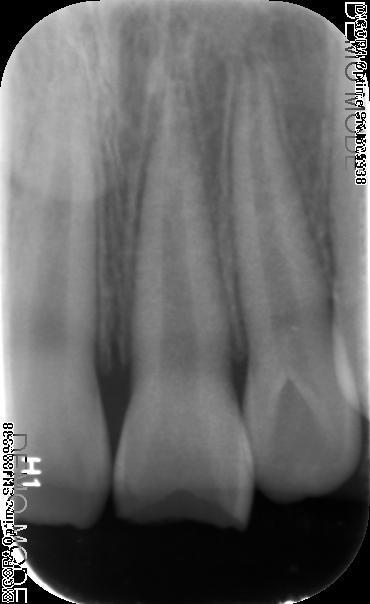

检查:#21 牙冠折断约2mm,叩(+-),松(I°),见露髓孔,冷热侧一过性敏感,电测无活力,牙龈稍红肿

诊断:#21冠折 治疗:#27碧兰麻下开髓,清理髓腔及根管,双氧水和生理盐水交替冲洗,测WL,拍片试尖达工作长度,根管内导入糊剂,侧压充填中下段,热牙胶充填上段,X线示恰填,树脂充填修复。